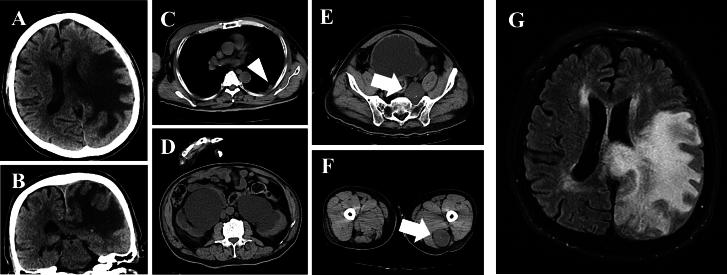

Schwannomatosis (SWN) is a rare genetic condition characterized by the risk of developing multiple benign peripheral nerve sheath tumors; however, the risk of developing malignant tumors in patients with SWN remains unclear. This study described the case of a 57-year-old Japanese man diagnosed with SWN whose older brother also had SWN. Whole-exome sequencing identified a heterozygous mutation [c.1018C > T (p.Arg340X)] in the gene, linked to the RAS/MAPK pathway, in the patient and his brother. Moreover, the patient had aphasia and right-sided paralysis because of a brain tumor. RNA sequencing revealed the remarkable upregulation of several genes associated with oxidative stress, such as the reactive oxygen species pathway and oxidative phosphorylation, a downstream effector of the RAS/MAPK pathway, in the the patient and his brother compared with healthy volunteers. The final diagnosis was -related familial SWN, and the dysregulated RAS/MAPK pathway in this patient might be associated with brain tumorigenesis.